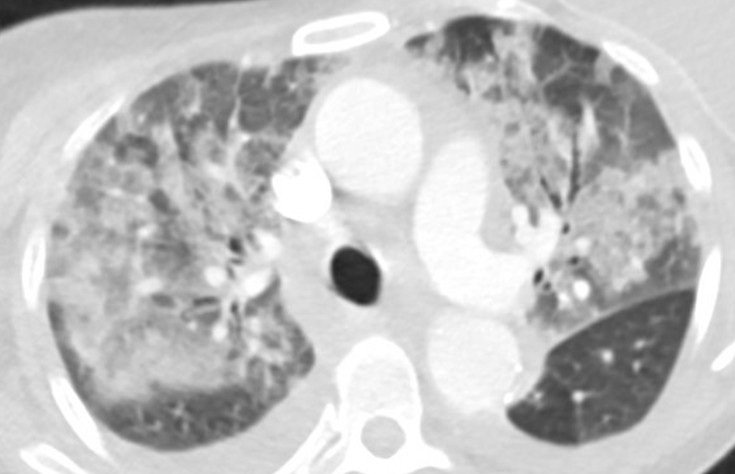

Figure 1. Axial “lung windows” reconstruction from a contrast-enhanced CT angiogram demonstrating mixed interstitial and airspace opacities consisting of smooth septal lines with patchy superimposed consolidation and ground glass with a central distribution (peripheral sparing). There are also small layering pleural effusions. Findings are nonspecific but would be considered consistent with “batwing edema” in the setting of severe alveolar edema given the clinical context. To view Figure 1 in a separate, enlarged window click here.

A 55-year-old woman with cirrhosis secondary to alcohol use disorder presented to the emergency department with worsening shortness of breath, orthopnea, and two recent syncopal episodes with seizure-like activity. She had undergone a transjugular intrahepatic portosystemic shunt (TIPS) procedure for refractory ascites one month prior. On arrival, she was hemodynamically stable but tachypneic (respiratory rate 22 bpm) with an SpO2 of 90% on room air. Her jugular venous pressure (JVP) was elevated. Chest X-ray showed bilateral pulmonary infiltrates. CT angiography (Figure 1) revealed bilateral patchy airspace disease with a central distribution and pleural effusions, suggesting alveolar edema. Abdominal imaging confirmed liver disease, ascites, and a TIPS. Laboratory tests revealed negative respiratory viral and SARS-CoV-2 PCR tests, ammonia was normal, BNP of 427 pg/mL, normal troponins, sodium 138 mmol/L, potassium 3.7 mmol/L, and procalcitonin 0.23 ng/mL. Blood and sputum cultures were collected. An electrocardiogram (ECG, figure-2B) showed sinus rhythm with QTc of 568 ms (baseline EKG Figure-2A). The patient was admitted to the step-down unit and started on broad-spectrum antibiotics for presumed pneumonia.